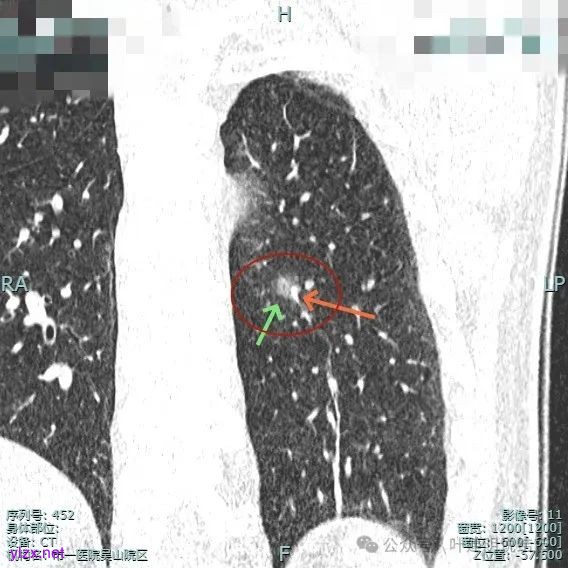

进入病灶内的血管壁毛糙不平,有异常增粗。

血管进入且异常增粗,其余部分密度为磨玻璃及少许点状偏高成分。

轮廓清,血管明显。

血管进入扭曲,毛刺明显,整体轮廓清,灶内小空泡征。